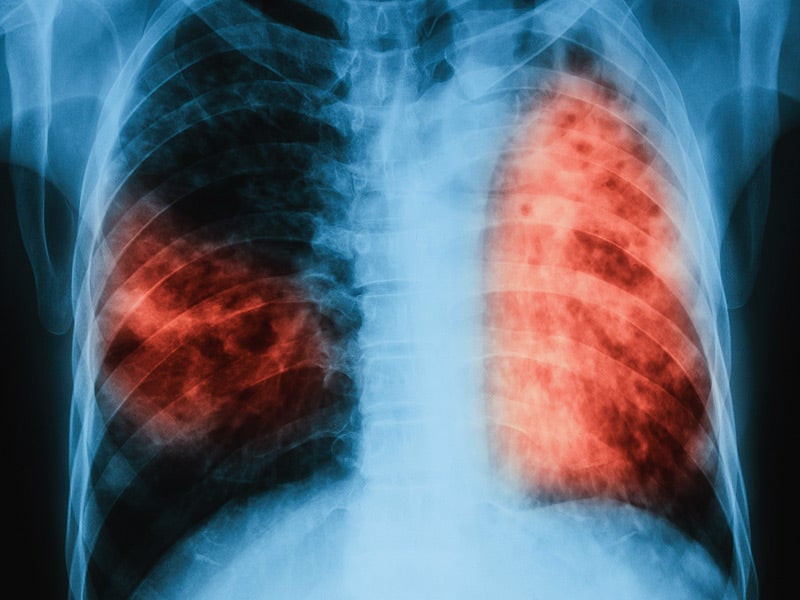

«Έξυπνο» σύστημα κάνει διαγνώσεις φυματίωσης

Επιστήμονες στις ΗΠΑ εκπαίδευσαν ένα σύστημα τεχνητής νοημοσύνης να μελετά ακτινογραφίες-Χ και να κάνει διαγνώσεις φυματίωσης. Το σύστημα αναμένεται να βοηθήσει μελλοντικά τους γιατρούς ...